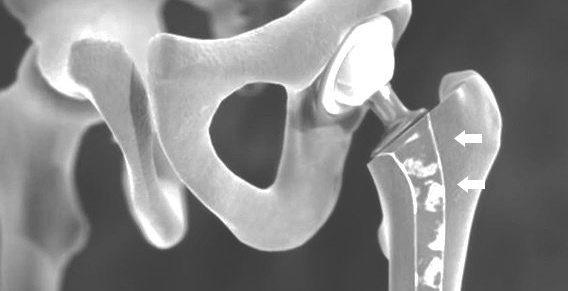

SUR L'ARTICULATION DE LA HANCHE, NOTAMMENT UNE INFECTION du matériau de la prothèse, UN POST-INTERMINATION PRÉCOCE DE LA TIGE ou une fracture de l'os impliquant les implants sont des complications à craindre.

L'OFT peut être réopéré avec un implant primaire de hanche lors du remplacement de la prothèse. Parfois, des implants de révision spéciaux sont également nécessaires.